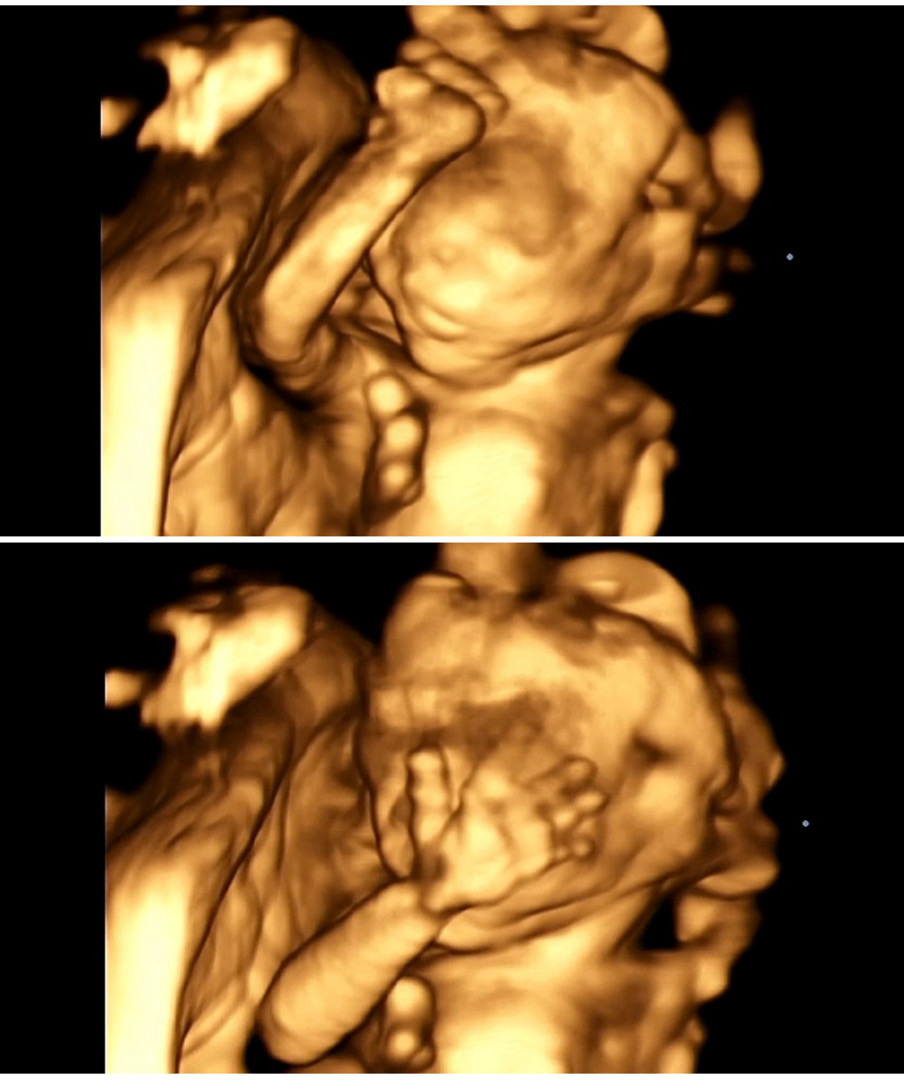

드뎌 공주 확정받고왔네요!! 💗

모두 딸이라 해주셔서 예상은 했지만 확정을 제대로 받으니 맘편해좋네요😚 다른베동님들도 확정받으셨나요~? 쑥쓰러워하는 뚝딱이 컷이네요 ㅎㅎ 너무움직여서 원장님이 애먹으셨다는 😅

손가락으로 가리는 모습 귀여워용